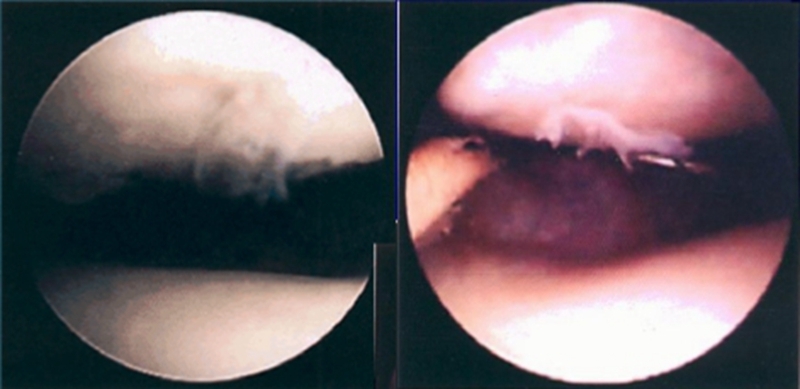

髌骨软化症Ⅰ级

髌骨软化症Ⅱ级

Ⅰ级:关节软骨失去珍珠样外观而变得较暗淡,局部软化,肿胀区或纤毛化区的直径<0.5cm。

Ⅱ级:关节软骨软化区内出现毛刷状或纤毛化改变,深达1-2mm,直径≤1.3cm。